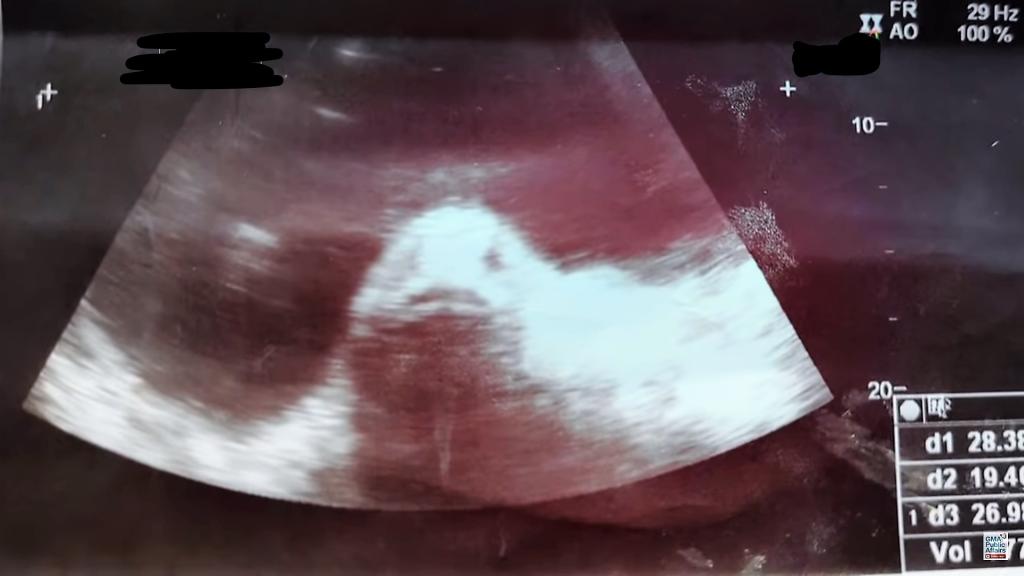

這起被形容為「海中異形入 侵少女體內致懷孕」的驚悚事件,發生於2017年6月份,卻於近日才在網路上引起一陣熱議,吸引不少國外媒體報導。而該少女超音波掃瞄照片也爆光,腹中竟然出現了「魚臉」!

家人以為她生活不檢點,在外面與男人胡亂搞關係,結果懷孕了,馬上就帶她上醫院檢查。醫生為貝茜娜進行了超音波掃瞄,螢幕上出現的竟然是「一條魚」,而且還露出了可愛的魚臉!

她再次回到醫院進行檢查,檢查報告竟然是卵巢囊腫,根本不是什麼魚寶寶!原來是巢囊腫,才讓她的體重一下子從40公斤飆升到50公斤,而且也會感覺疼痛。